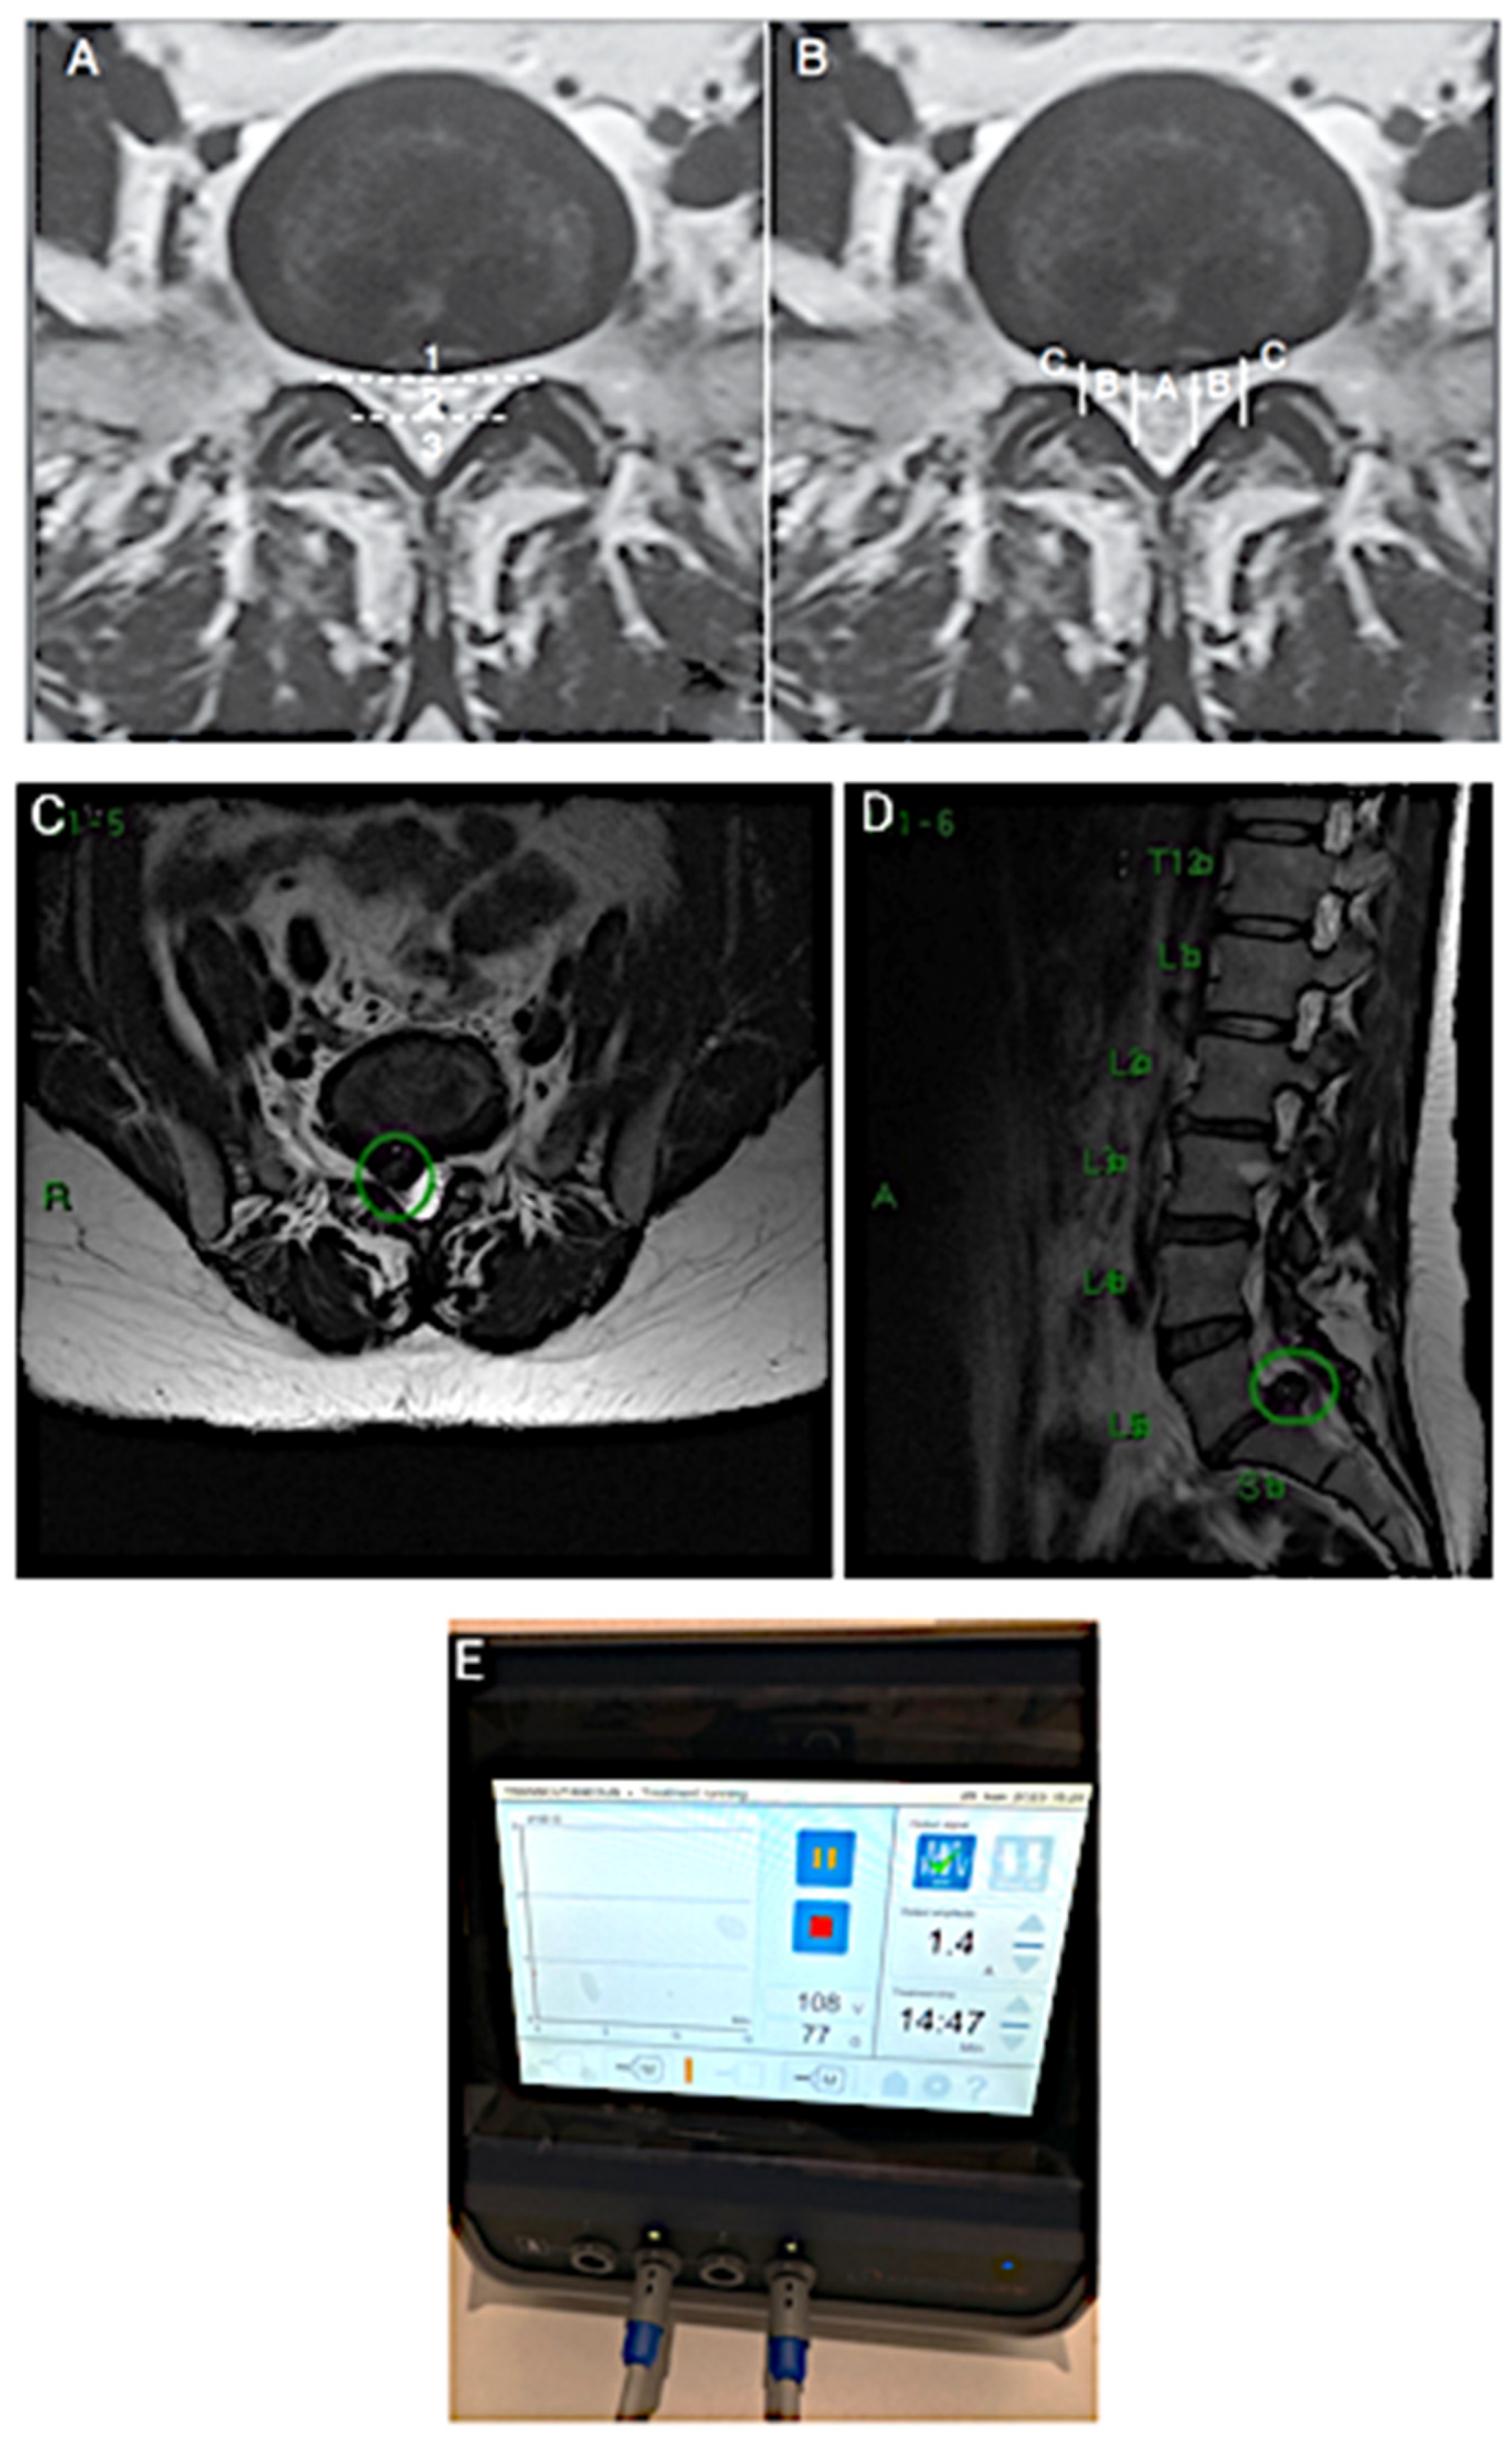

2. CASE 1: Lumbar Root Pain